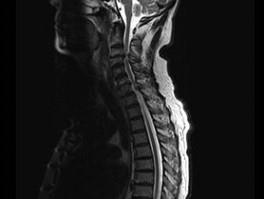

问题 男,65岁,颈部疼痛,双下肢无力3月余,请结合影像学检查,选出最可能的诊断 ( )

选项 A、小关节面综合征 B、椎管狭窄 C、脊膜瘤 D、脊膜膨出 E、脊髓空洞症

答案 B